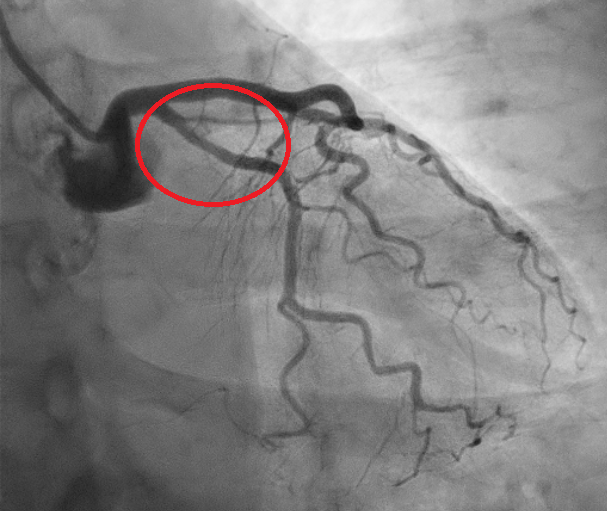

We report the case of a 61-year-old woman presenting with chest pain radiating to the left arm. EKG showed inferolateral repolarization abnormalities. Laboratory revealed mild elevation in troponin (0.76). Transthoracic echocardiography demonstrated mildly reduced systolic function with posterolateral wall akinesia (ejection fraction 48%). The patient was referred for coronary angiography showing no significant stenoses; however, a focal narrowing of the proximal circumflex artery (LCX) was observed, consistent with type 3 spontaneous coronary artery dissection (SCAD) according to the Yip–Saw classification (Fig. 1). Given the risk of iatrogenic propagation of the dissection and recommendations to minimize coronary instrumentation in SCAD, intracoronary imaging was avoided, and we performed instead coronary computed tomography angiography (CCTA) demonstrating mild stenosis of the LCX with mural hyperdensity, consistent with an intramural hematoma (Fig. 2). On day four, the patient experienced angina similar to the initial episode, with ECG changes and an increase in troponin (1.2). Repeat coronary angiography demonstrated progression of the dissection from the LCX to the distal segment of the first obtuse marginal branch, corresponding to evolution toward type IIb SCAD (Fig. 3). Given the limited myocardial territory at risk and the absence of ongoing symptoms, conservative management was continued. Patient was discharged on day ten on a beta-blocker and aspirin.with a planned follow-up CCTA at six months. This case highlights that in SCAD, particularly type 3 and proximal lesions, a conservative approach is often the safest strategy, with non-invasive imaging playing a key role in diagnosis, follow-up, and therapeutic guidance.